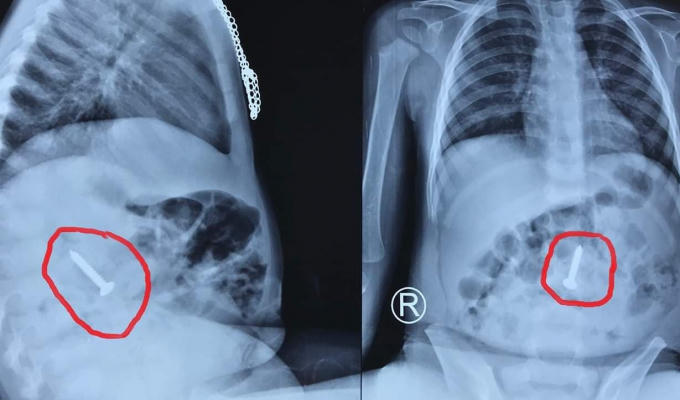

Hình ảnh chụp Xquang cho thấy chiếc đinh vít ở trong cơ thể bệnh nhi.

Trước đó, vào ngày 14/6, bệnh viện Hữu nghi đa khoa Nghệ An tiếp nhận bệnh nhi Ng.H.H (20 tháng tuổi) với chẩn đoán nuốt phải dị vật kim khí. Kết quả nội soi cho thấy, tại đoạn cuối tá tràng của bệnh nhi có hình ảnh dị vật kim loại một đầu sắc nhọn (ốc vít kim loại) dài 3,5 cm. Chiếc đinh vít có một đầu rất sắc nhọn có thể đâm thủng ruột, dạ dày của trẻ, gây nguy hiểm đến tính mạng.